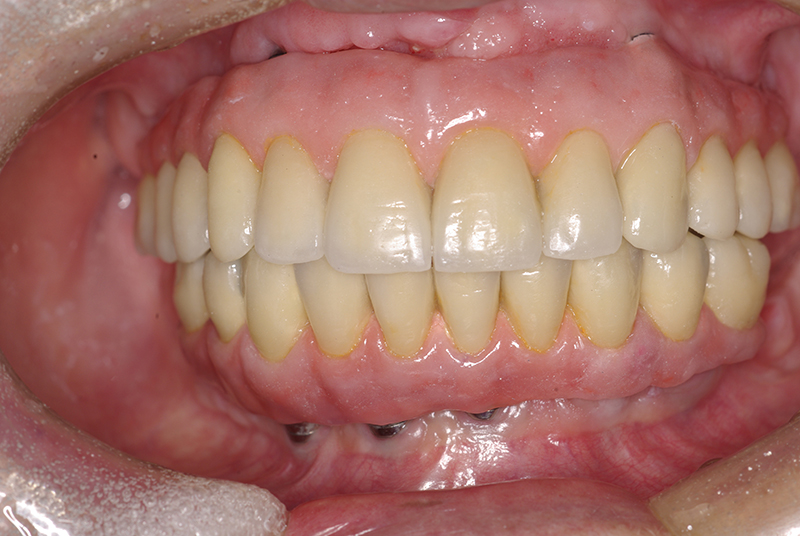

Na Clínica Pontes Odontologia, somos referência em implantes dentários em Fortaleza, oferecendo tratamentos de alta qualidade e tecnologia de ponta. Os implantes dentários são estruturas de titânio posicionadas cirurgicamente no osso maxilar ou mandibular para substituir as raízes dos dentes ausentes. Essa técnica permite a fixação de próteses personalizadas, restaurando a função mastigatória, a estética e a autoestima dos nossos pacientes.

Utilizamos a tecnologia CAD CAM, um sistema avançado que possibilita a confecção precisa das próteses dentárias diretamente sobre os implantes. Esse método inovador garante um ajuste perfeito, um resultado estético superior e proporciona muito mais conforto e durabilidade. Com o CAD CAM, nossos pacientes contam com um processo mais rápido e previsível para alcançar o sorriso desejado.